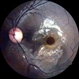

- traumatic macular hole, human amniotic graft

- A 24 year old male patient presented with history of injury at workplace followed by loss of vision. He had a intraocular foreign body with a large traumatic macular hole. Patient was operated and the intraocular foreign body was removed. The hole was too large to close by ILM so an AMG graft was used. Patient regained 20/120 vision.